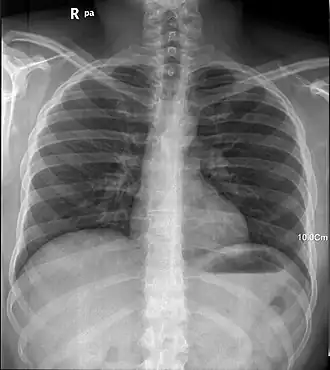

- При помощи рентгеновских лучей можно «просветить» человеческое тело, в результате чего можно получить изображение костей, а в современных приборах и внутренних органов (см. также рентгенография и рентгеноскопия). При этом используется тот факт, что у содержащегося преимущественно в костях элемента кальция (Z = 20) атомный номер гораздо больше, чем атомные номера элементов, из которых состоят мягкие ткани, а именно водорода (Z = 1), углерода (Z = 6), азота (Z = 7), кислорода (Z = 8). Кроме обычных приборов, которые дают двумерную проекцию исследуемого объекта, существуют компьютерные томографы, которые позволяют получать объёмное изображение внутренних органов.